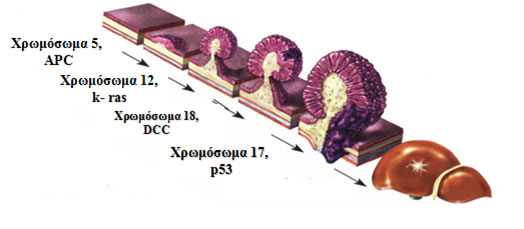

Ο καρκίνος του παχέος εντέρου είναι προϊόν ενός εξαλλαγμένου πολύποδα, γεγονός που συμβαίνει με μία σειρά γενετικών, ιστολογικών και μακροσκοπικών αλλαγών και φαινομένων (φυσιολογικός βλεννογόνος- αδενωματώδης πολύποδας- καρκίνος in situ- διηθητικός καρκίνος), οι οποίες έχουν περιγραφεί αναλυτικά από τον Vogelstein και είναι γνωστές ως αλληλουχία αδενώματος-καρκινώματος (Εικόνα 3).

Εικόνα 3.

Αλληλουχία αδενώματος-καρκινώματος. Συσσώρευση γονιδιακών μεταλλάξεων οδηγούν στην πρόδο της ορθοκολικής καρκινογένεσης

(Τροποποιημένο από: P. H. Gordon, S. Nivatvongs “Principles and Practice of Surgery for the Colon, Rectum, and Anus”)

Η κακοήθης νόσος είναι γενετική και η πρόοδος από το φυσιολογικό βλεννογόνο στο αδένωμα και στη συνέχεια στο αδενοκαρκίνωμα οφείλεται στην άθροιση γενετικών ελλειμμάτων.

Δύο βασικά γενετικά μονοπάτια διέπουν την καρκινογένεση στο παχύ έντερο:

Στο 70% των σποραδικών καρκίνων και στην οικογενή αδενωματώδη πολυποδίαση (FAP):

- Το μονοπάτι της χρωμοσωμικής αστάθειας ή της απώλειας ετεροζυγωτίας, στο οποίο υπεύθυνο είναι το ογκοκατασταλτικό γονίδιο APC (Αdenomatous Polyposis Coli), το οποίο εντοπίζεται στο χρωμόσωμα 5 (5q21).

- Στο μονοπάτι αυτό, στην αλληλουχία αδενώματος-καρκινώματος βασικό ρόλο παίζουν τα γονίδια k-ras και p